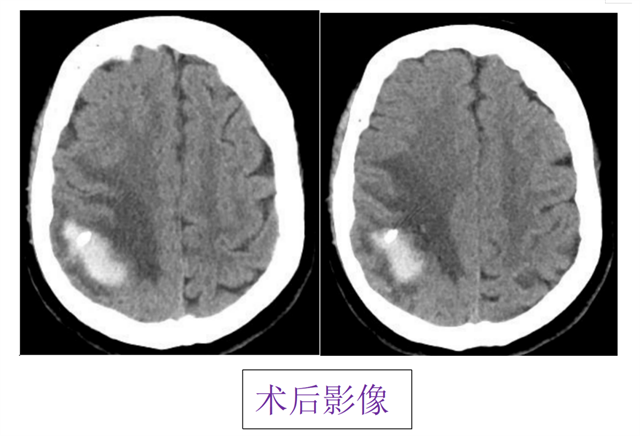

手术机器人一种微创治疗方式

能精准定位、迅速改善患者神经功能症状

该技术具有

创伤小、定位准、出血少、恢复快

四大优势

可显著降低患者术后

并发症风险及死亡率

为后续康复治疗赢得宝贵时间